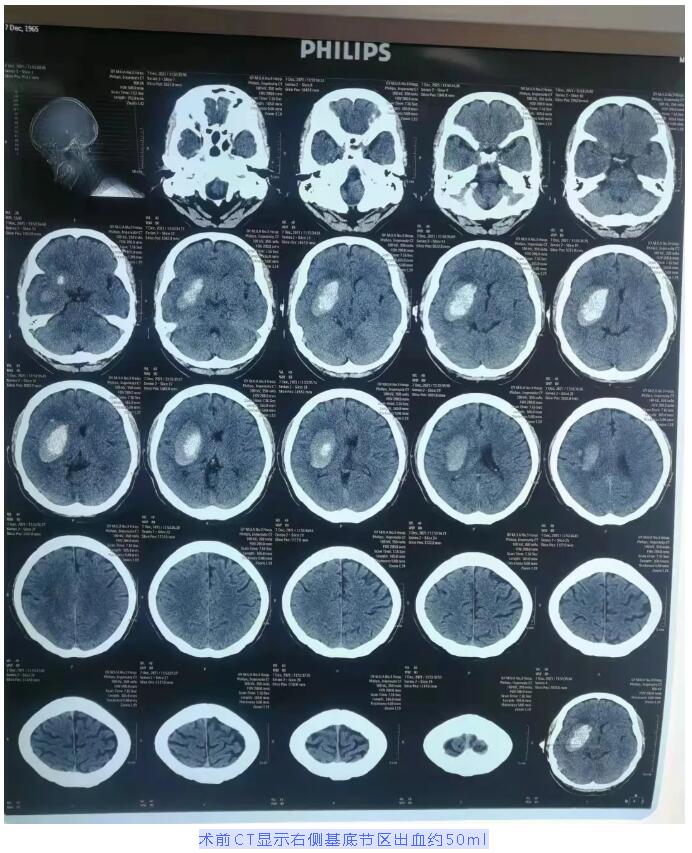

56岁的蒙先生因突发左侧肢体无力伴言语不清,被家属紧急送到我院神经外科抢救。入院时,蒙先生嗜睡,瞳孔对光反射迟钝,右侧肢体肌力5级,左侧肢体肌力1级。头颅CT显示为右侧基底节区脑出血。诊断为:右侧基底节区脑出血、脑疝形成、原发性高血压3级极高危组。

蒙先生在第一时间接受了3D打印导航立体定向下右侧颞部微创穿刺颅内血肿引流术。通过3D打印技术,精准穿刺到血肿中心位置,术中抽出暗血性血凝块约22ml,手术顺利。